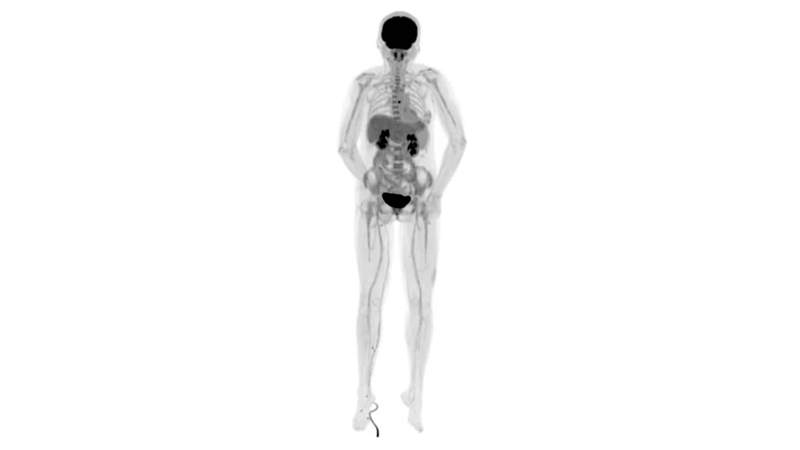

直腸癌

男,45歲,直腸癌術(shù)后9個月,發(fā)現(xiàn)肺占位

臨床診斷:直腸區(qū)術(shù)后改變,復(fù)發(fā)伴骶骨受累,雙肺多發(fā)轉(zhuǎn)移